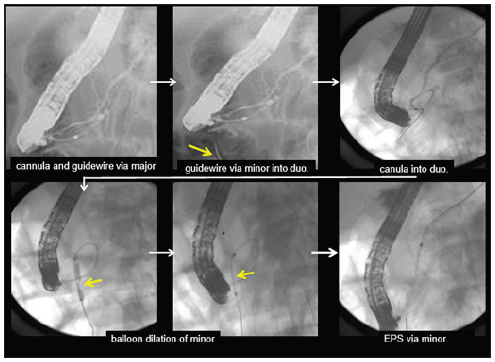

Case 1 56-year old male: The guidewire, inserted through the major papilla, came out into the duodenum via the minor papilla. Along this guidewire, the minor papilla was cut by a needle type papillotome (KD-200Q-0721 Olympus) and the catheter was inserted into the minor papilla, then EPS was placed. This is our original procedure, a variant of the rendezvous method [1].

Case 2 13-year old female: She entered into our hospital complaining of reccurent epigastralgia. The guidewire, inserted into the major papilla, came out via Wirsung’s duct, connecting branch, Santorini’s duct and minor papilla into the duodenum. The minor papilla was cut by needle type papillotome (rendezvous pre-cut method), and a balloon catheter was inserted along the guidewire and the minor papilla was dilated from the reverses direction by a 4mm dilation balloon, then EPS could be placed into the dorsal duct [1].

Figure 1: Rendezvous precut method: guidewire came back into the duodenum and pre-cutting of the minor was done then catheter was inserted into Santorini-duct.

Figure 2: Rendezvous precut method: guidewire came back into the duodenum and pre-cutting of the minor was done then catheter was inserted into Santorini-duct.